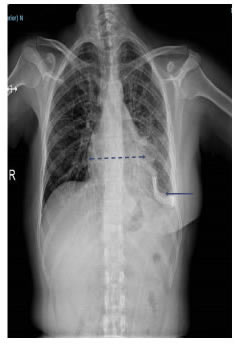

En la radiografía de tórax se observó derrame pleural izquierdo y aumento del tamaño de la silueta cardiomediastínica (figura 9).En la TC de tórax se apreciaba derrame pericárdico, con tabiques, derrame pleural izquierdo, y engrosamiento pleural y pericárdico (figura 10).

Se le practicó una ventana pericárdica izquierda mediante toracotomía asistida por video (VATS) y se le instaló un catéter subcutáneo (tunnelized) pleuro-pericárdico temporal (figura 11).